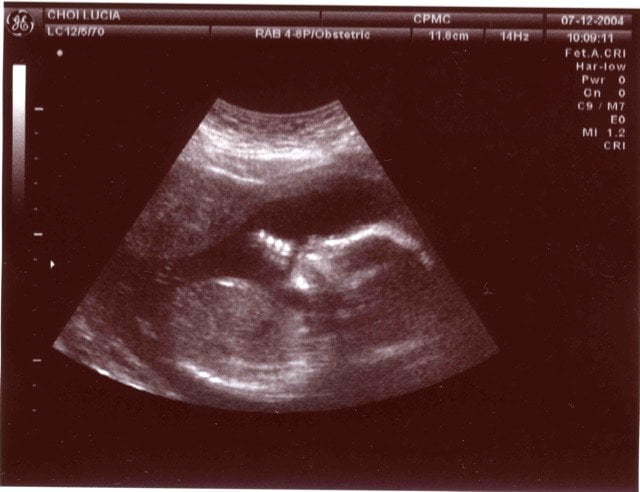

Moviendo la sonda y girándola se va barriendo la zona a estudiar, y el ordenador conectado a ella va traduciendo los datos obtenidos a partir de las ondas reflejadas en píxeles, que forman una “rodaja” del cuerpo. Lo que se obtiene con una de estas ecografías normales y corrientes es una imagen bidimensional de esa “rodaja”:

En primer lugar, como has visto en varias de las imágenes del artículo, las ecografías se utilizan muchísimo en obstetricia. Como mencioné en los artículos de las otras tomografías, se hace todo lo posible por no utilizar radiaciones “duras” cuando hay niños involucrados: lo mismo sucede, por supuesto, durante el embarazo. La ecografía es una técnica muchísimo más segura que cualquiera de las otras, pues no existe ningún tipo de prueba clínica que haya demostrado peligro para el ser humano, ni siquiera durante la gestación, al ser expuesto a los ultrasonidos de estas frecuencias.